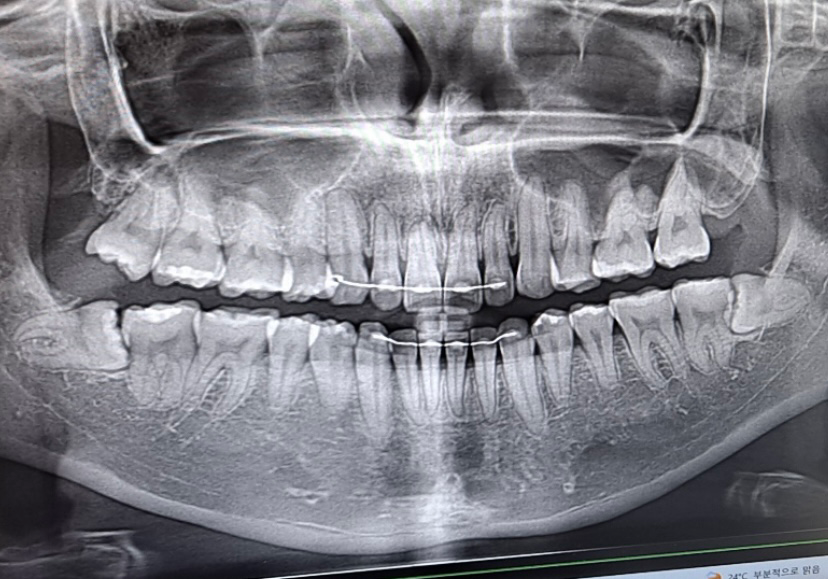

충치로 보이는 치아가 몇 개 정도 있을까요?

혹시 이 엑스레이에서 충치로 의심되는 치아가 몇 개인지 알 수 있을까요?

윗니 1~13

아랫니 14~29(매복사랑니 포함)

혹시 보이신다면 번호로 얘기해주시면 감사하겠습니다ㅠㅠ

파노라마 사진으로는 심한 충치가 보이지는 않습니다.

치아 홈에 생긴 충치는 엑스레이에는 보이지 않고 육안상으로만 보이는 경우가 있어요.

엑스레이 상으로는 크게 충치가 진행되건 없어 보입니다. 보이는 갈색은 변색이나 착색됫을 가능성이 높습니다.

씹는면 충치는 방사선 사진, 특히 파노라마 방사선 사진으로는 관찰이 어렵습니다

검은 줄이나 점은 초기 충치인 경우가 많으며 상태로 봐서 크게 치료가 필요하지 않다고 판단했기 때문에 그렇게 말씀하신 것일 겁니다

양치질만 잘하고 6개월에 한번씩 정기검진만 하시면 될 것 같습니다

추가적으로 확인이 필요한 치아는 아래쪽 사랑니 앞 두번째 큰 어금니 2개와 우측 첫번째 큰 어금니 입니다.